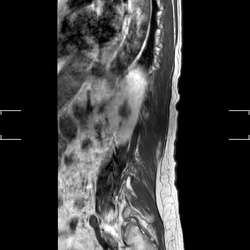

MRI_MobiView_Sag_T2W_TSE_403

21 photos